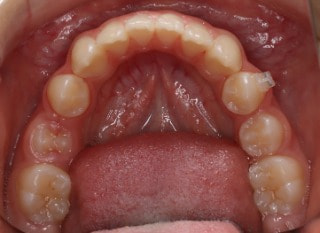

小児期第二段階

開始時